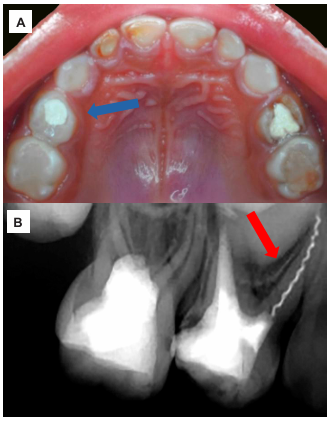

Una paciente pediátrica de sexo femenino, de 4 años y 11 meses de edad, acudió de urgencia a la Clínica de Odontopediatría de la Universidad Privada San Juan Bautista (Lima, Perú), acompañada de su madre. Esta refirió que su hija estaba recibiendo tratamiento del conducto cuando, al momento de finalizar el sellado, realizó un movimiento inesperado, lo que provocó la fractura del instrumento endodóntico. En el examen clínico odontológico, la niña mostró un comportamiento positivo, según la Escala de Frankl (16). El primer molar superior deciduo del lado derecho presentaba una restauración temporal (figura 1A) y dolor a la percusión vertical. Radiográficamente, en la pieza 54 se observó una imagen radiopaca (IRO) coronal compatible con una restauración. Además, se identificó una IRO intraconducto en la raíz distovestibular, sugestiva de material de obturación del conducto radicular; y, en la raíz mesiovestibular, se evidenció una IRO compatible con un léntulo fracturado de aproximadamente 7 mm de longitud, con aparente sobrepaso apical.

Asimismo, se observó un ensanchamiento del espacio del ligamento periodontal en la superficie distal de la raíz mesiovestibular. A nivel interradicular, se identificó una imagen radiolúcida (IRL) con pérdida de la lámina dura, junto con reabsorción radicular en el tercio apical de la pieza (figura 1B). El diagnóstico pulpar fue de tratamiento de conducto previo, mientras que el diagnóstico periapical correspondió a periodontitis apical sintomática del primer molar superior deciduo, con fractura de un instrumento en el conducto mesiovestibular. Se indicó la extracción del instrumento endodóntico fracturado, seguido de un retratamiento del conducto radicular.

Figura 1 Examen clínico y radiográfico de la pieza 54. A) Vista oclusal del maxilar superior, en la que se observa la pieza 54 con restauración temporal. B) Radiografía periapical de la pieza 54, donde se observa imagen radiopaca proyectada en raíz mesiovestibular compatible con fractura de instrumento endodóntico.